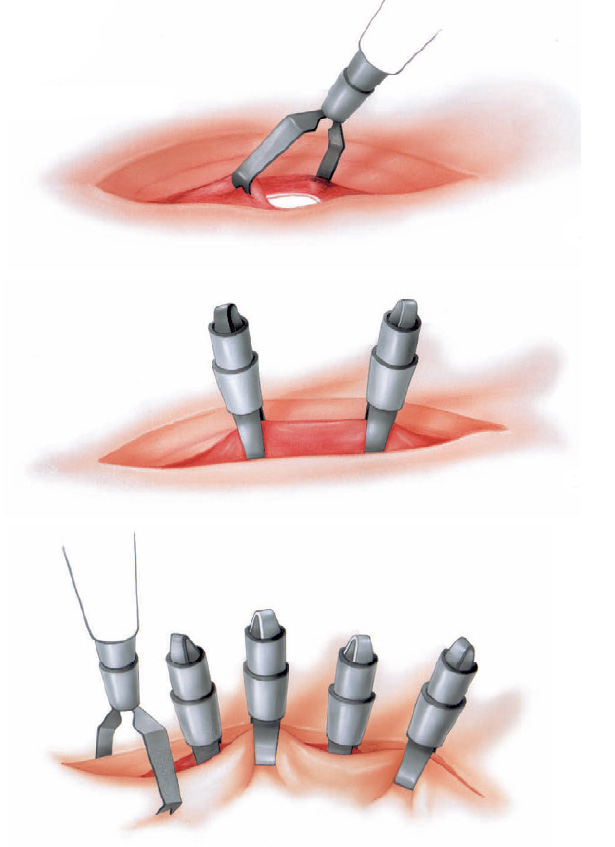

O que acontece durante o procedimento?

Para a gastrostomia endoscópica percutânea, você receberá um sedativo e um anestésico local para mantê-lo sem sentir dor. O médico irá introduzir um endoscópio através de sua boca até o seu estômago. Um endoscópio é um tubo fino e flexível com uma pequena câmera. Ele permite que o médico olhe para o interior de seu estômago durante o procedimento.

O seu médico irá encher o estômago com ar para torná-lo maior e empurrar a parede do estômago mais perto da parede abdominal. O médico irá guiar uma agulha e fio através de sua pele e parede abdominal até o seu estômago. O endoscópio permite ao médico ver e capturar o fio dentro do estômago.

O fio é então puxado de volta pela boca. Um tubo de plástico é ligada ao fio e puxado através da boca ao longo do percurso até o estômago.

O médico irá fixar o tubo de dentro do estômago e na sua pele. O pedaço curto do tubo de borracha visível através da parede abdominal é facilmente coberto com a roupa.